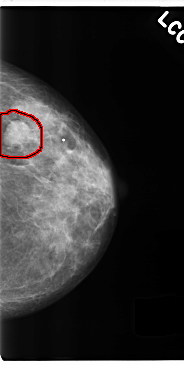

FILE: C_0212_1.LEFT_CC.OVERLAY

TOTAL_ABNORMALITIES 1

ABNORMALITY 1

LESION_TYPE MASS SHAPE OVAL MARGINS CIRCUMSCRIBED

ASSESSMENT 4

SUBTLETY 5

PATHOLOGY MALIGNANT

TOTAL_OUTLINES 1

BOUNDARY